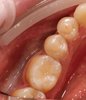

• Эстетическая реставрация зубов композитными материалами

- Эстетическая стоматология

Виниры, вкладки, циркониевые коронки

Работа с оптическим увеличением. Композитные/керамические виниры, вкладки (inlay,onlay, overlay)

Эстетическое восстановление всех групп зубов композитами светового отверждения

Реставрации зубов.